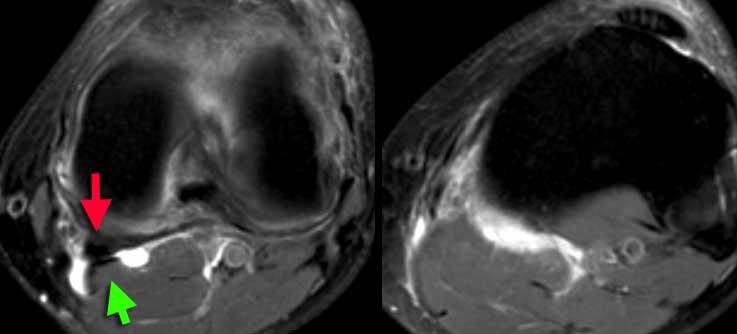

Hội chứng ma sát dải chậu chày

Vị trí ma sát bất thường thường gặp là giữa dải chậu chày và lồi cầu ngoài, hay xảy ra ở vận động viên đi bộ tốc độ cao, đạp xe và đôi khi ở người chạy bộ.

Khi túi hoạt dịch hình thành tại vị trí này, tình trạng này được gọi là ‘Hội chứng ma sát dải chậu chày’.

Hình bên trái là một vận động viên đi bộ tốc độ cao với triệu chứng đau mặt ngoài gối.

Bình thường phải có mô mỡ giữa dải chậu chày và lồi cầu ngoài, nhưng trong trường hợp này mô mỡ không còn hiện diện.

Hội chứng ma sát dải chậu chày: Dịch trong túi hoạt dịch thấy được giữa dải chậu chày và xương đùi (mũi tên vàng). Dịch khớp dừng lại tại các mũi tên đỏ.

Cùng bệnh nhân trên. Trên các lát cắt axial, có thể thấy dịch trong túi hoạt dịch nằm giữa dải chậu chày và xương đùi bên dưới.

Đôi khi cần phân biệt dịch tại vị trí này với dịch khớp.

Cần xem xét toàn bộ các lát cắt hình ảnh.

Trong trường hợp này, dịch khớp dừng lại tại các mũi tên đỏ.